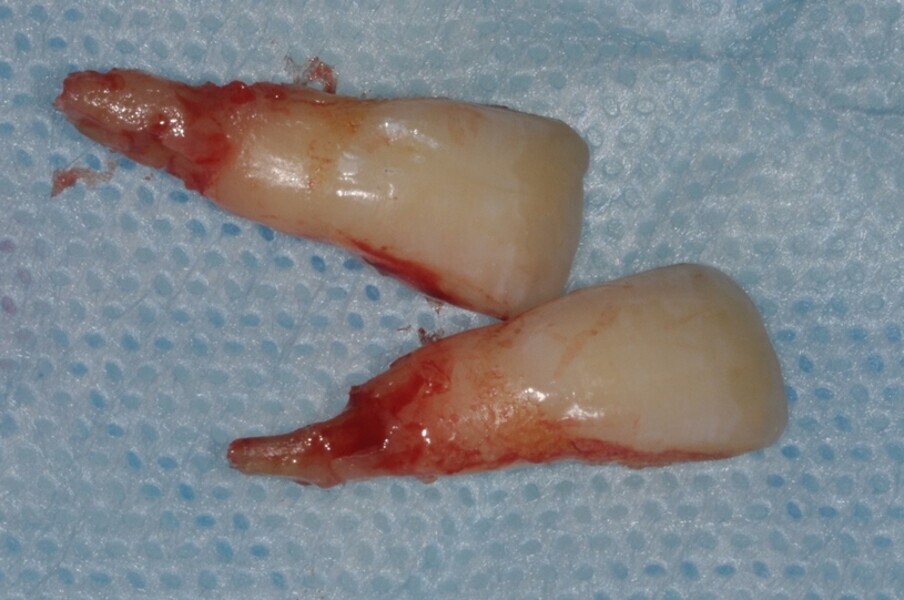

Ryc. 3_Zęby 11 i 21 po ekstrakcji.